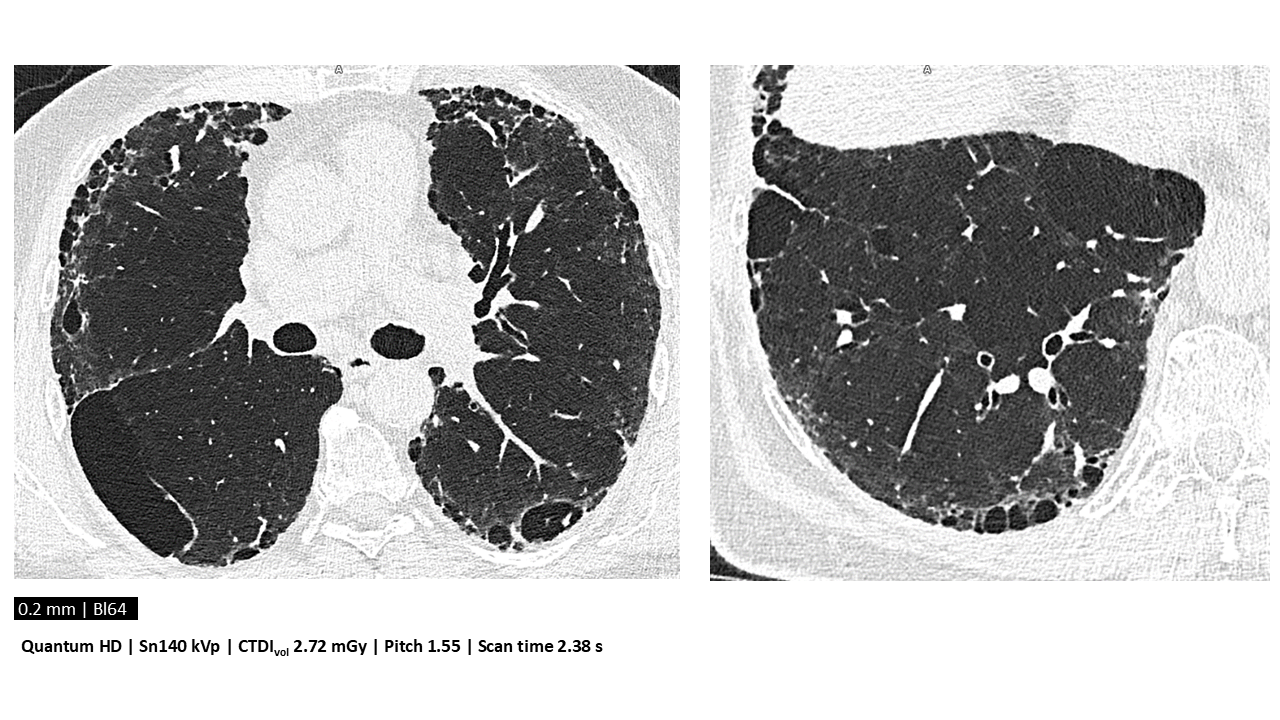

In this part of her talk, Dr. Teo introduced photon-counting CT as the next leap in transforming medical imaging. With submillimeter resolution and reduced radiation, scanners like the NAEOTOM Alpha enable reclassification of ILDs and lower-dose follow-ups.

“You can now see what used to be a blur. But if your post-processing can’t keep up, it’s like watching HD on a broken screen.”